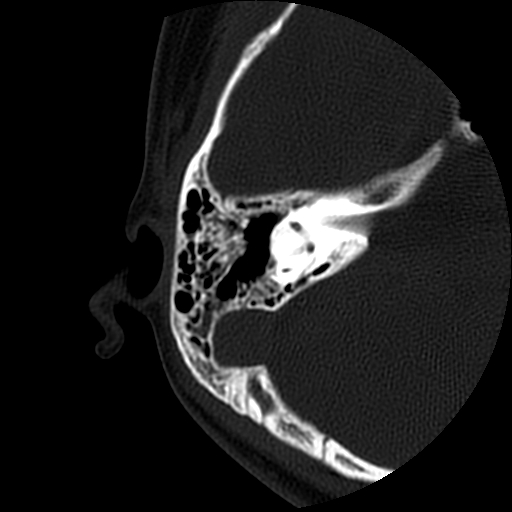

以下是引用随光逐影在2009-8-19 7:25:00的发言:[br]右侧慢性中耳乳突炎,右侧中耳腔及外耳道肉芽肿或胆脂瘤形成。